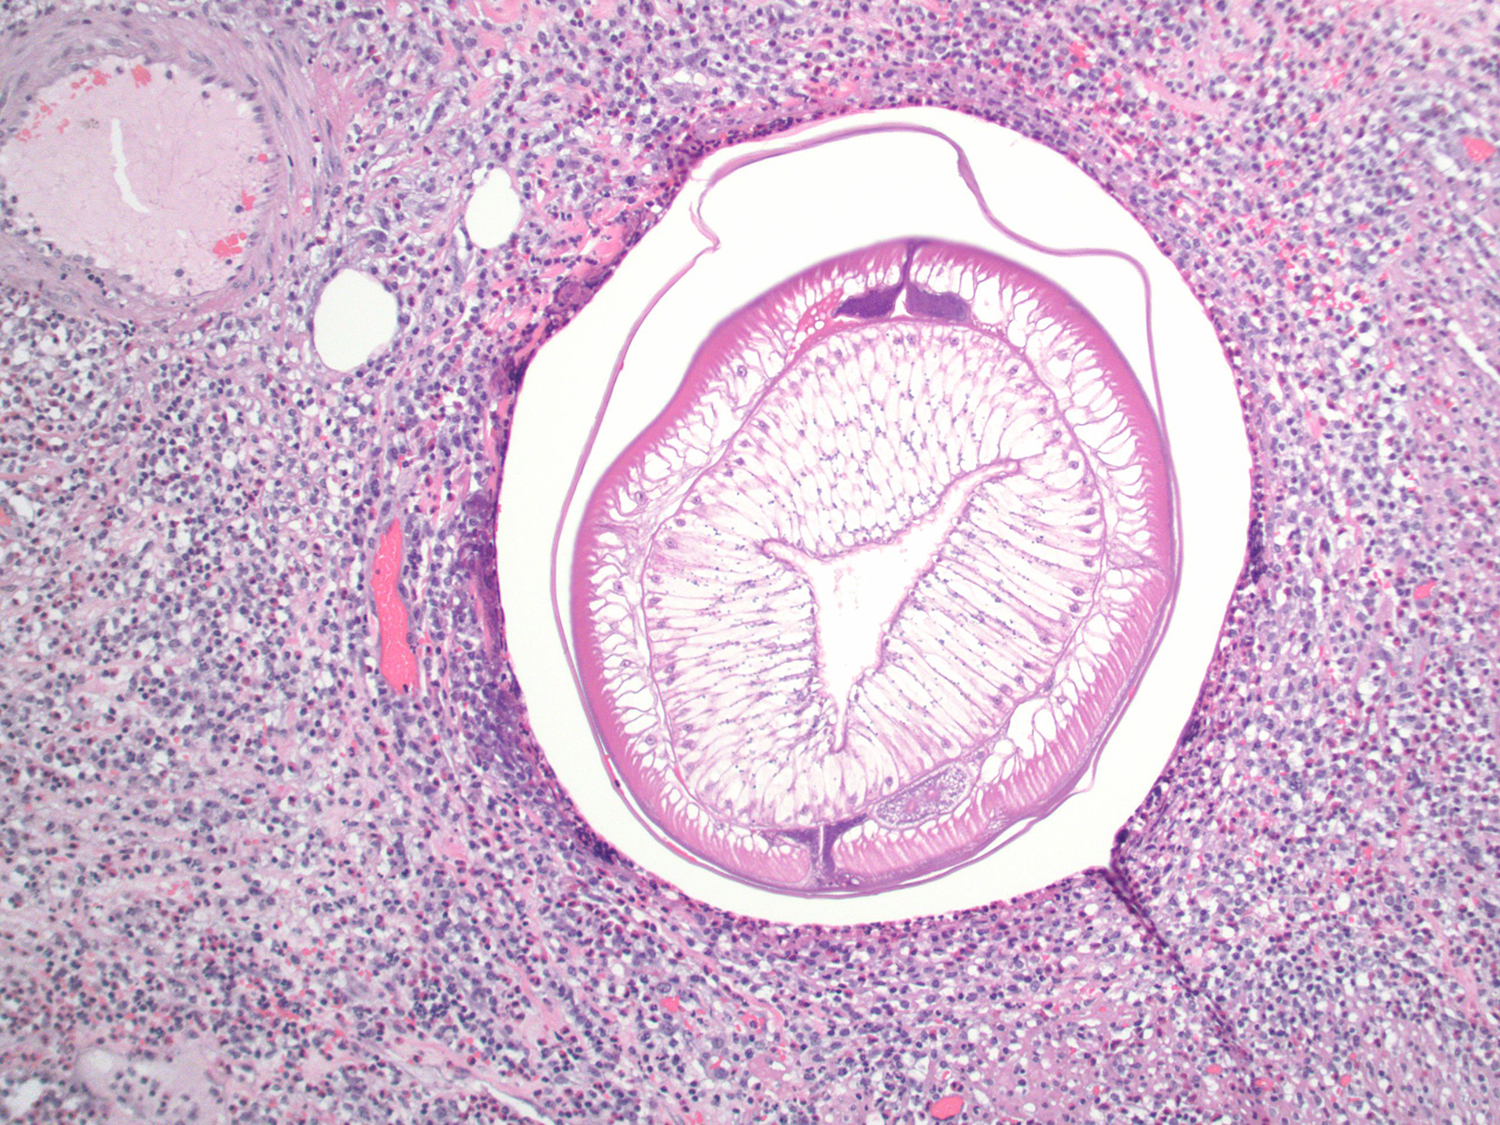

This week's case was generously donated by Dr. Karra Jones. A patient presented with intestinal intussusception, and the following was seen on histopathologic examination of the resected bowel. What is your diagnosis?

10x objective:

Answer to the Parasite Case of the Week 751: Anisakis species.

Thanks to all who provided comments on this case! Idzi kicked us off with his comment: "The Y-shaped lateral chords tell me that this is patient has eaten raw (or undercooked) fish! 😉". Florida Fan then elaborated, "The cross sections tell us that this is a nematode. From online publications and Idzi's comment, the very tall musculature and Y-shaped lateral chords favor a diagnosis of anisakiasis."

Here is an annotated image showing some of the key features: